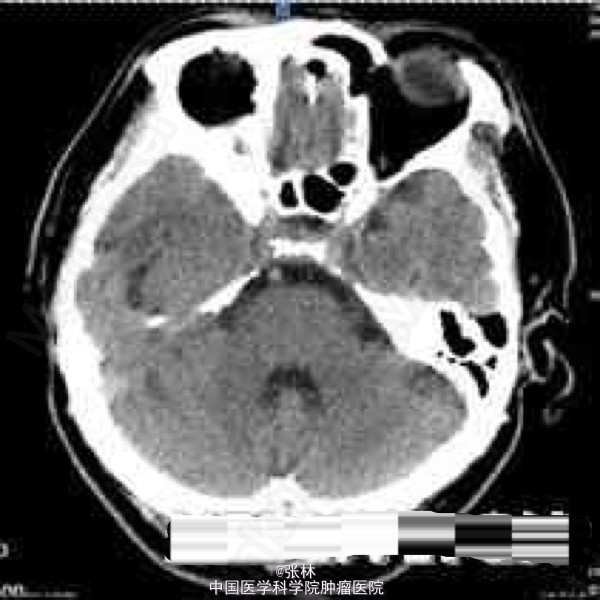

CT表现:右侧颅中窝可见一不规则肿块,呈等密度,内部密度均匀,CT值约37HU,肿块边界尚清晰,略成分叶状,与邻近骨质呈广基底相连,最大截面3.3cm×3.8cm,边缘处可见带状低密度影,边界清晰,CT值约16HU。肿块周边脑组织水肿,密度略减低。肿块周边骨质未见增厚硬化或变薄等异常改变(图1-2)。 CT诊断:右侧颅中窝肿块,伴周围脑组织水肿,建议进一步检查。 MRI表现:右侧颅中窝可见一不规则肿块,最大截面3.6cm×4.1cm,肿块边界清晰,成分叶状,与邻近骨质呈广基底相连(图5-6),在T1WI上呈等信号,在T2WI上呈略高信号;肿块边缘可见不规则液性信号带,在T1WI上呈低信号,在T2WI上呈高信号,与脑组织分界清楚(图3-4);肿块前方颞叶部分脑组织可见片状异常信号,在T1WI上呈稍低信号,在T2WI上呈略高信号,边缘模糊(图3-4);注射对比剂后,肿块实性部分明显强化,并可见“脑膜尾征”,而液性信号带未见强化(图5-6),肿块前方颞叶的片状异常信号未见强化。 MRI诊断:右侧颅中窝脑膜瘤,部分囊变,伴周围脑组织水肿。 手术病理结果:非典型性脑膜瘤,WHO分级II级。 讨论: 脑膜瘤是颅内仅次于胶质瘤的常见原发肿瘤,发病率占颅内肿瘤的16%~17%,在颅内脑外原发肿瘤中占第一位。它起源于脑膜的蛛网膜内皮细胞,常见于富含蛛网膜颗粒与蛛网膜绒毛的地方,以上矢状窦旁、大脑凸面、大脑镰、蝶骨嵴、鞍结节、嗅沟、小脑桥脑角区及小脑幕等部位多见。